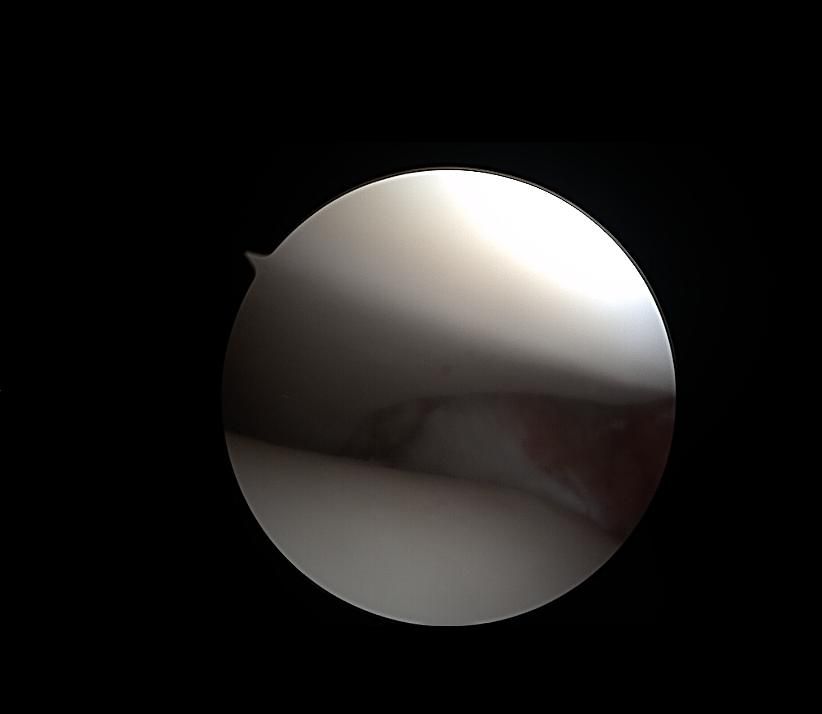

제가 발목 연골손상이라 mri와 내시경 사진이 있는데

어떤 상태인지 좀 다른 고견을 들어보고자 합니다

• 1번 째 사진

현재 연골 손상이 있으신 것으로 보이는데요, 올려주신 사진이 참고에 도움이 될 수 있으나 정확한 소견을 말씀드리기에는 어려움이 있으므로 정확한 소견은 주치의에게 들어보시는 것이 좋겠습니다.